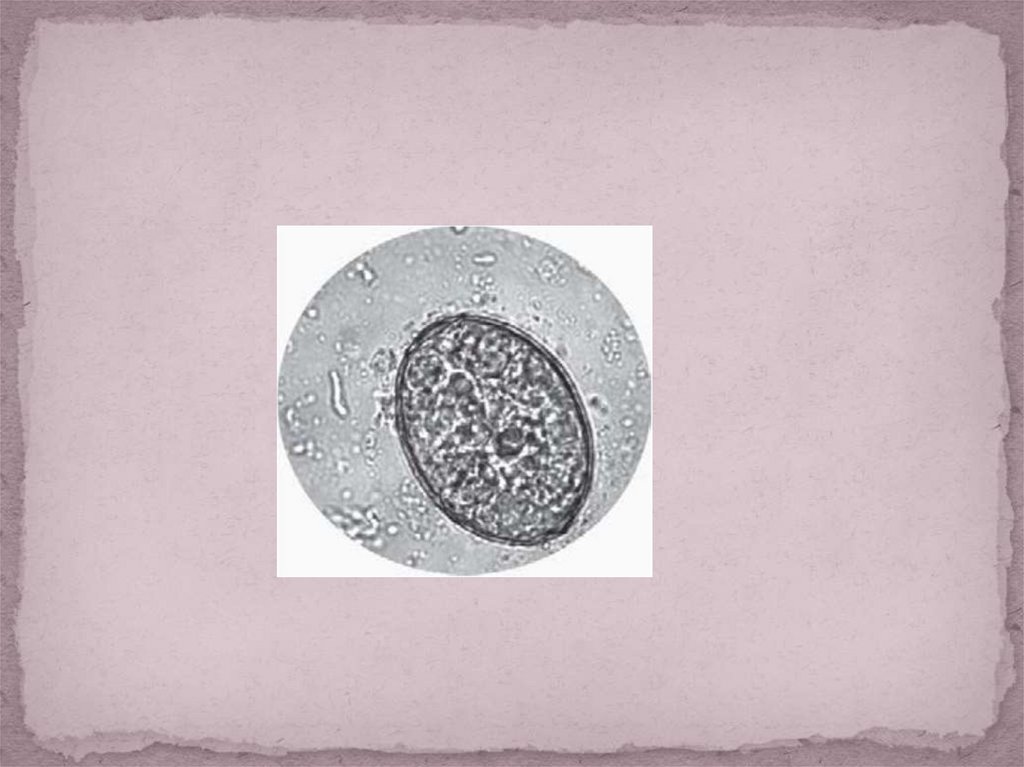

Яйца размером около 55-85 мкм на 40-60 мкм, овальные с

мелким боковым корешком или шишечкой.